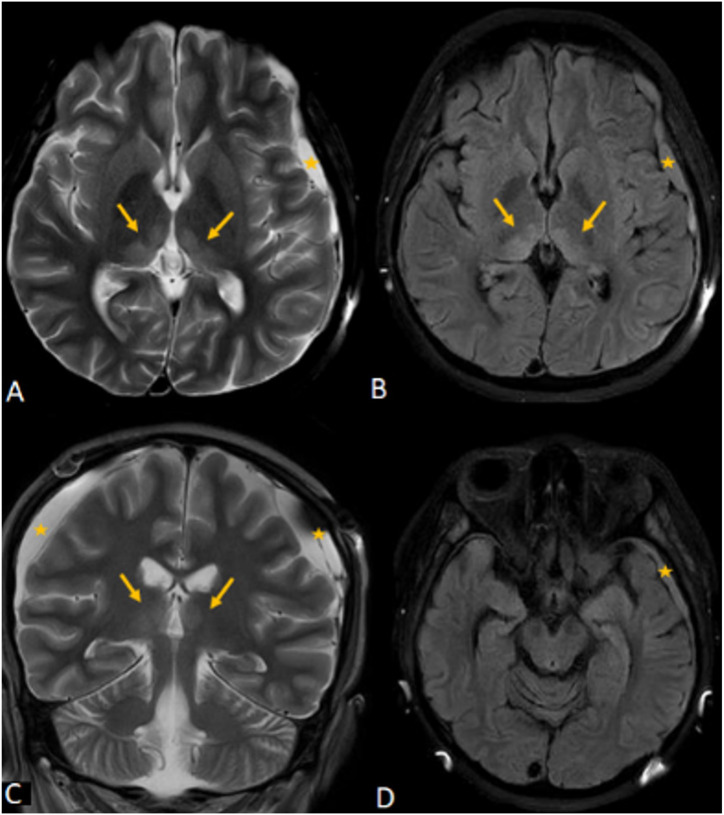

16岁急性髓性白血病女孩长时间全肠外营养所致韦尼克脑病。

Wernicke Encephalopathy Induced by Prolonged Total Parenteral Nutrition in a 16-Year-Old Girl with Acute Myeloid Leukemia.